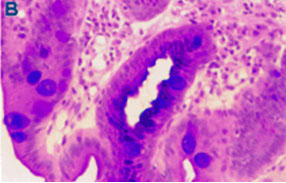

Dysplasia in Barrett esophagus. A) Abrupt transition from Barrett metaplasia to low-grade dysplasia (arrow).  B) Architectural irregularities, including gland-within-gland, or cribriform profiles in high-grade dysplasia